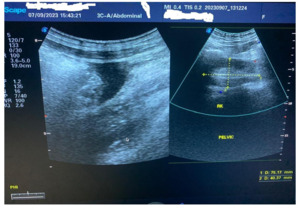

The ultrasound scan showed an enlarged hypoechoic spleen measuring 10.5 cm x 10.0 cm x 6.3 cm. Splenic infarct/abscess and hepatomegaly were detected. Echo-containing intra-abdominal free fluid (pus) with the deepest pocket was 62 mm. The left kidney was in the normal anatomical location, but the right kidney was in the pelvis (Figure 1). The CT scan was unavailable.